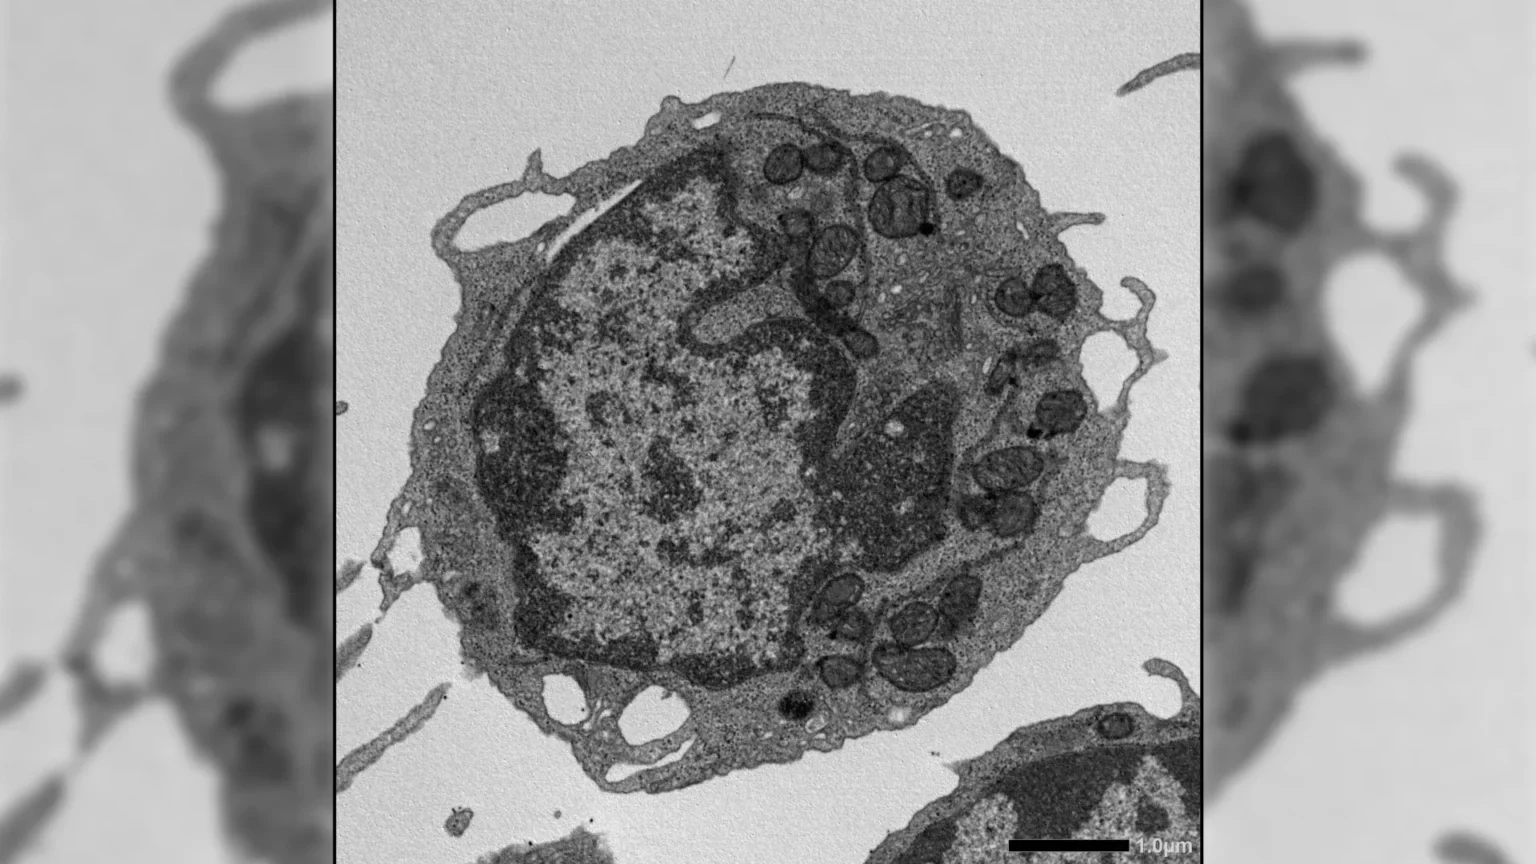

When activated under stress, MLKL transiently moved to mitochondria, the energy-producing structures in cells. There, damage was caused by a decrease in membrane potential, changes in mitochondrial structure, and decreased energy production. These effects resulted in important features of HSC aging, such as decreased self-renewal capacity, decreased production of lymphoid cells, and transition to production of myeloid cells.